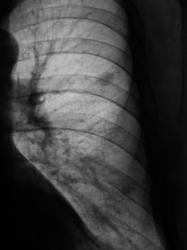

Зафиксировано увеличение тени в размерах. Произведена рентгенография в прямой стандартной проекции.

Было высказано предположение о наличии "маленького периферического рака", зафиксирована "линзеподобная тень" паракостально. Пациент направлен на консультацию в онкологический диспансер.

Окружающая легочная ткань - 2008 и 2009 г.